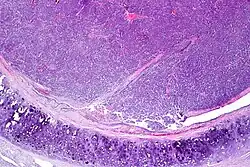

| Atypical pulmonary carcinoid. H&E stain. | |

Atypical pulmonary carcinoid tumour is a subtype of pulmonary carcinoid tumor.[1] It is an uncommon low-grade malignant lung mass that is most often in the central airways of the lung. It is also known as "atypical lung carcinoid tumour", " atypical lung carcinoid" or "moderately differentiated neuroendocrine carcinoma".

Atypical carcinoid tumors have increased mitotic activity (2-10 per 10 HPF), nuclear pleomorphism or foci of necrosis.